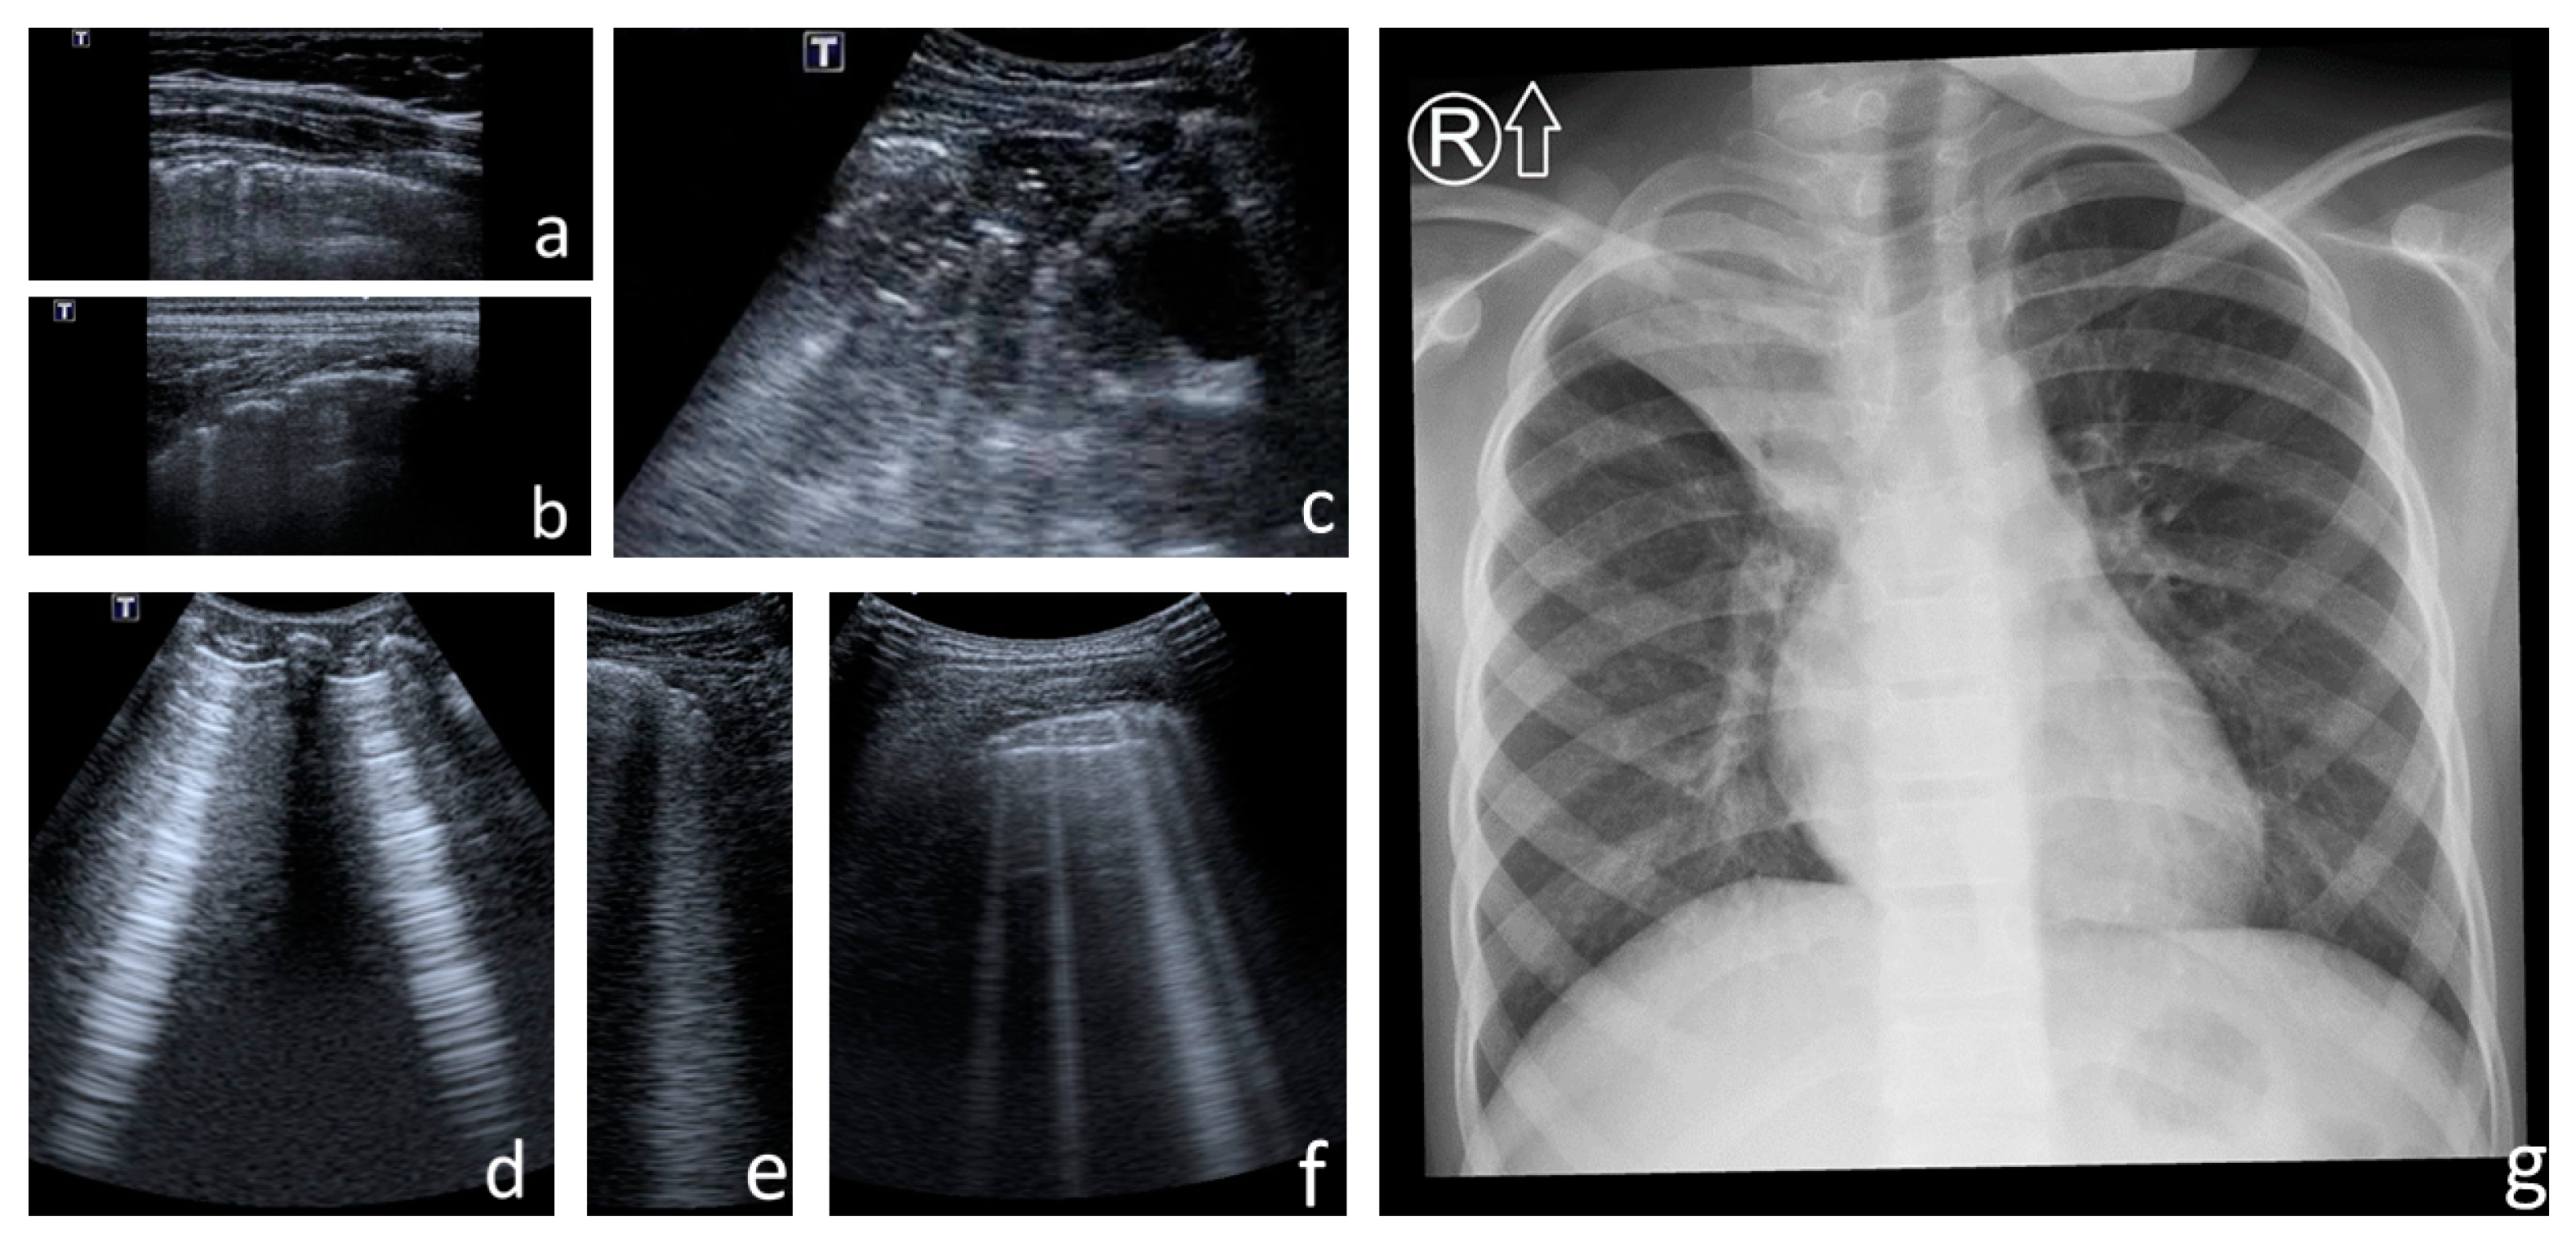

- Consolidations—hypoechoic, tissue-like areas: (a) small (≤10 mm) (Figure 6), and (b) major (>10 mm) (Figure 7); usually, major consolidations have the following associated features: the loss of pleural line echogenicity over the area of consolidation, absence of A-lines, presence of dynamic or static air bronchogram/air trapping and vascular pattern (in CD option) within the area, C-lines below the area, B-lines surrounding it [17,31];